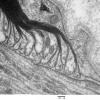

PERIPHERAL NEUROPATHY

3 NORMAL MYELIN & SCHWANN CELLS

2 Node of Ranvier (2)